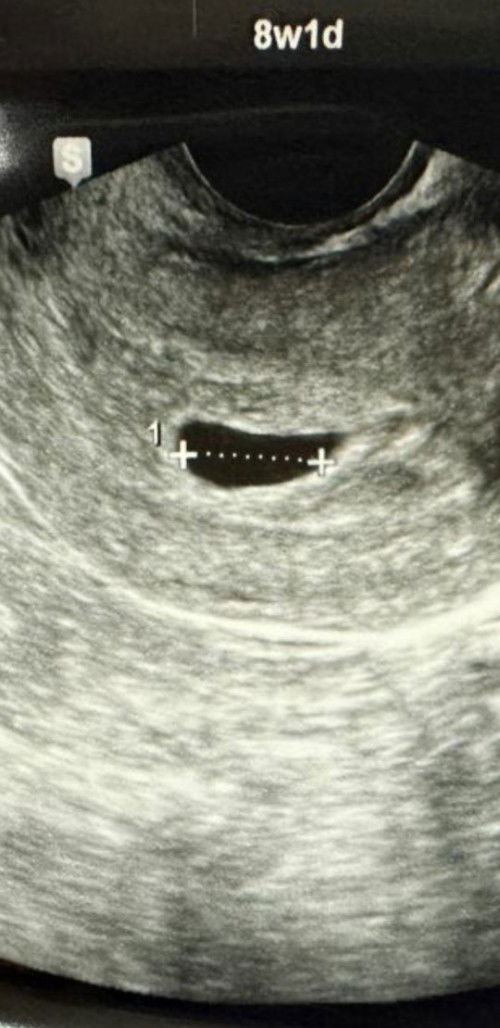

8w tp kntung kita mcm ni? ada pontensi utk menjadi x sbb doc ckp kntong ksong dan xmnjadi 😔😌😔

Dktr kata mcmtu sbb bentuk kantung x membulat spt sepatutnya. Tp just monitor dlu, if ada spotting / cramp cepat2 pi klinik check semula